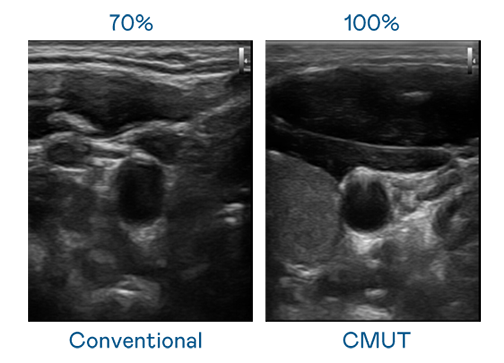

申博太陽(yáng)城運(yùn)用 TFT 陣列 (Array) 制程延伸尖端感測(cè)技術(shù) ,開(kāi)發(fā)出多種感測(cè)元件的產(chǎn)品。高解析度、品質(zhì)穩(wěn)定且可量產(chǎn)的 CMUT 元件,可制作高解析度超音波探頭、貼片型探頭 ,對(duì)病患實(shí)施精準(zhǔn)檢測(cè)與長(zhǎng)時(shí)間生理監(jiān)測(cè) 。為滿足 X光設(shè)備輕量化、可移動(dòng) ,甚至需針對(duì)待測(cè)物進(jìn)行外觀客制化的新需求 ,申博太陽(yáng)城結(jié)合非晶矽 (a-Si) 制程與新的封裝技術(shù),實(shí)現(xiàn)可撓曲、具優(yōu)異 TFT 遷移率 (mobility) 的柔性 X光感測(cè)器。目前也已提供完整玻璃和曲面型 X光感測(cè)器檢測(cè)解決方案 。